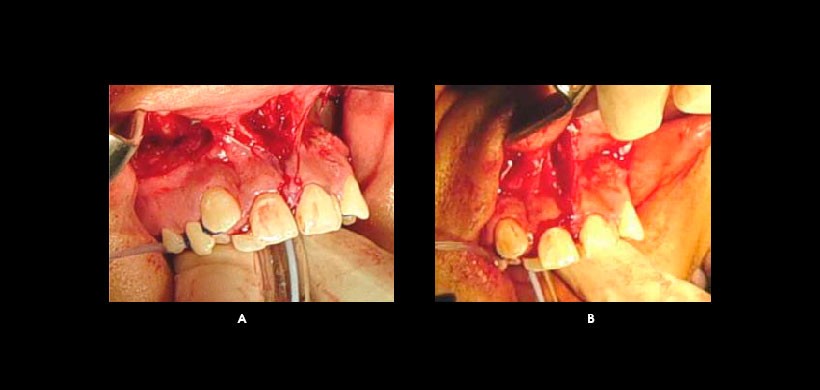

Figura 2: A) La incisión se realiza por encima de los ápices de los incisivos en dirección de la espina nasal anterior. B) Separación del septo nasal; se realiza una osteotomía vertical, utilizando cincel.